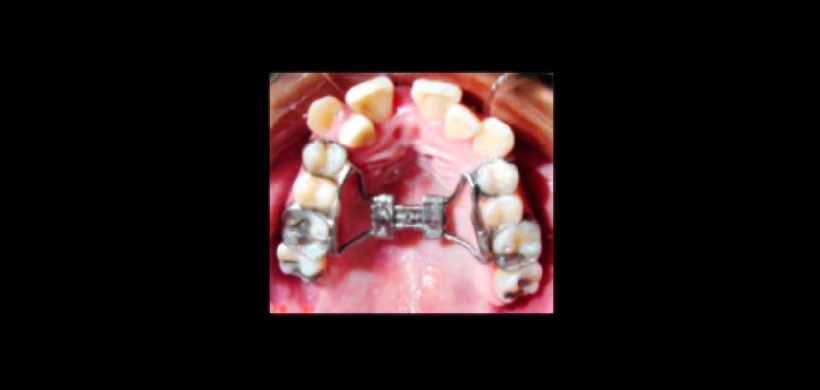

Figura 3: Colocación y activación del tornillo de expansión